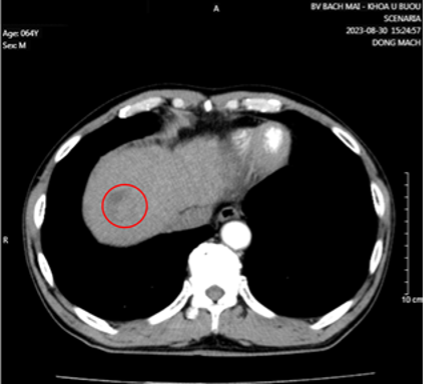

- Cắt lớp vi tính lồng ngực có tiêm thuốc cản quang:

Hình 1. Khối u kích thước 51x58x42mm thùy trên phổi trái, ngấm thuốc không đều sau tiêm (vòng tròn đỏ).

Hình 3: Nhu mô hạ phân thùy VII có vài khối, nốt kích thước lớn nhất 33x26mm giảm tỷ trọng trước tiêm, ngấm thuốc thì động mạch (vòng tròn đỏ), thải thuốc thì tĩnh mạch cửa (vòng tròn).